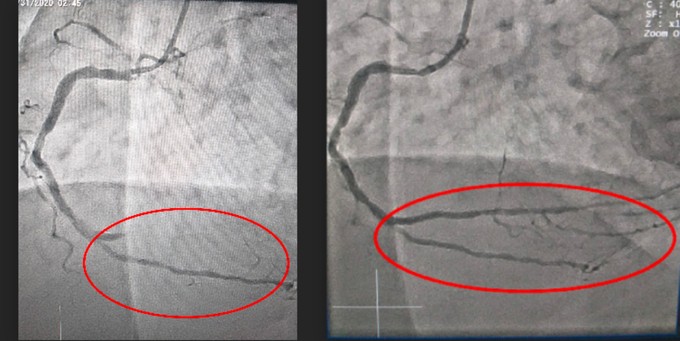

Bằng hệ thống máy chụp mạch máu kỹ thuật số xóa nền (DSA), các bác sĩ đã nong và đặt stent mạch vành cho bệnh nhân thành công. Hiện, sức khỏe bà ổn định và hồi phục tốt.